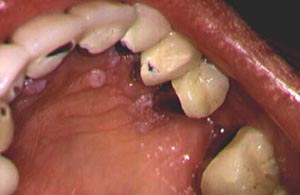

People with human immunodeficiency virus (HIV), the virus that causes acquired immunodeficiency syndrome (AIDS), are at special risk for oral health problems. Some of the most common oral problems for people with HIV/AIDS are: chronic dry mouth, gingivitis, bone loss around the teeth (periodontitis), canker sores, oral warts, fever blisters, oral candidiasis (thrush), hairy leukoplakia (which causes a rough, white patch on the tongue), and dental caries. Combination antiretroviral therapy, which is used to treat the HIV condition and restore immune system function, has made some oral problems less common. Oral conditions can be painful, annoying, and can lead to other problems.Read More